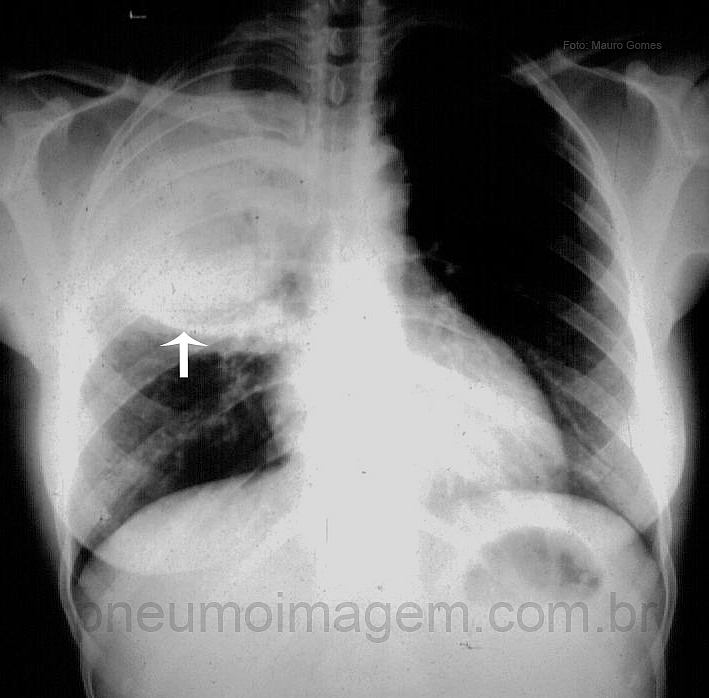

CASO CLÍNICO #17Paciente do sexo feminino, 48 anos, tabagista, etilista crônico, apresenta-se com tosse com expectoração avermelhada, febre e dor torácica há 4 dias. Observe a radiografia de entrada, faça a sua hipótese diagnóstica e deixe seus comentários abaixo.

Female patient, 48, smoker and chronic alcoholic patient presents with cough with reddish sputum, fever and chest pain for 4 days. Note the chest X-ray, make your diagnosis and leave your comments below.

pneumonia por klebsiella

pneumonia do lobo pesado causada por klebsiella.

Abscesso Pulmonar